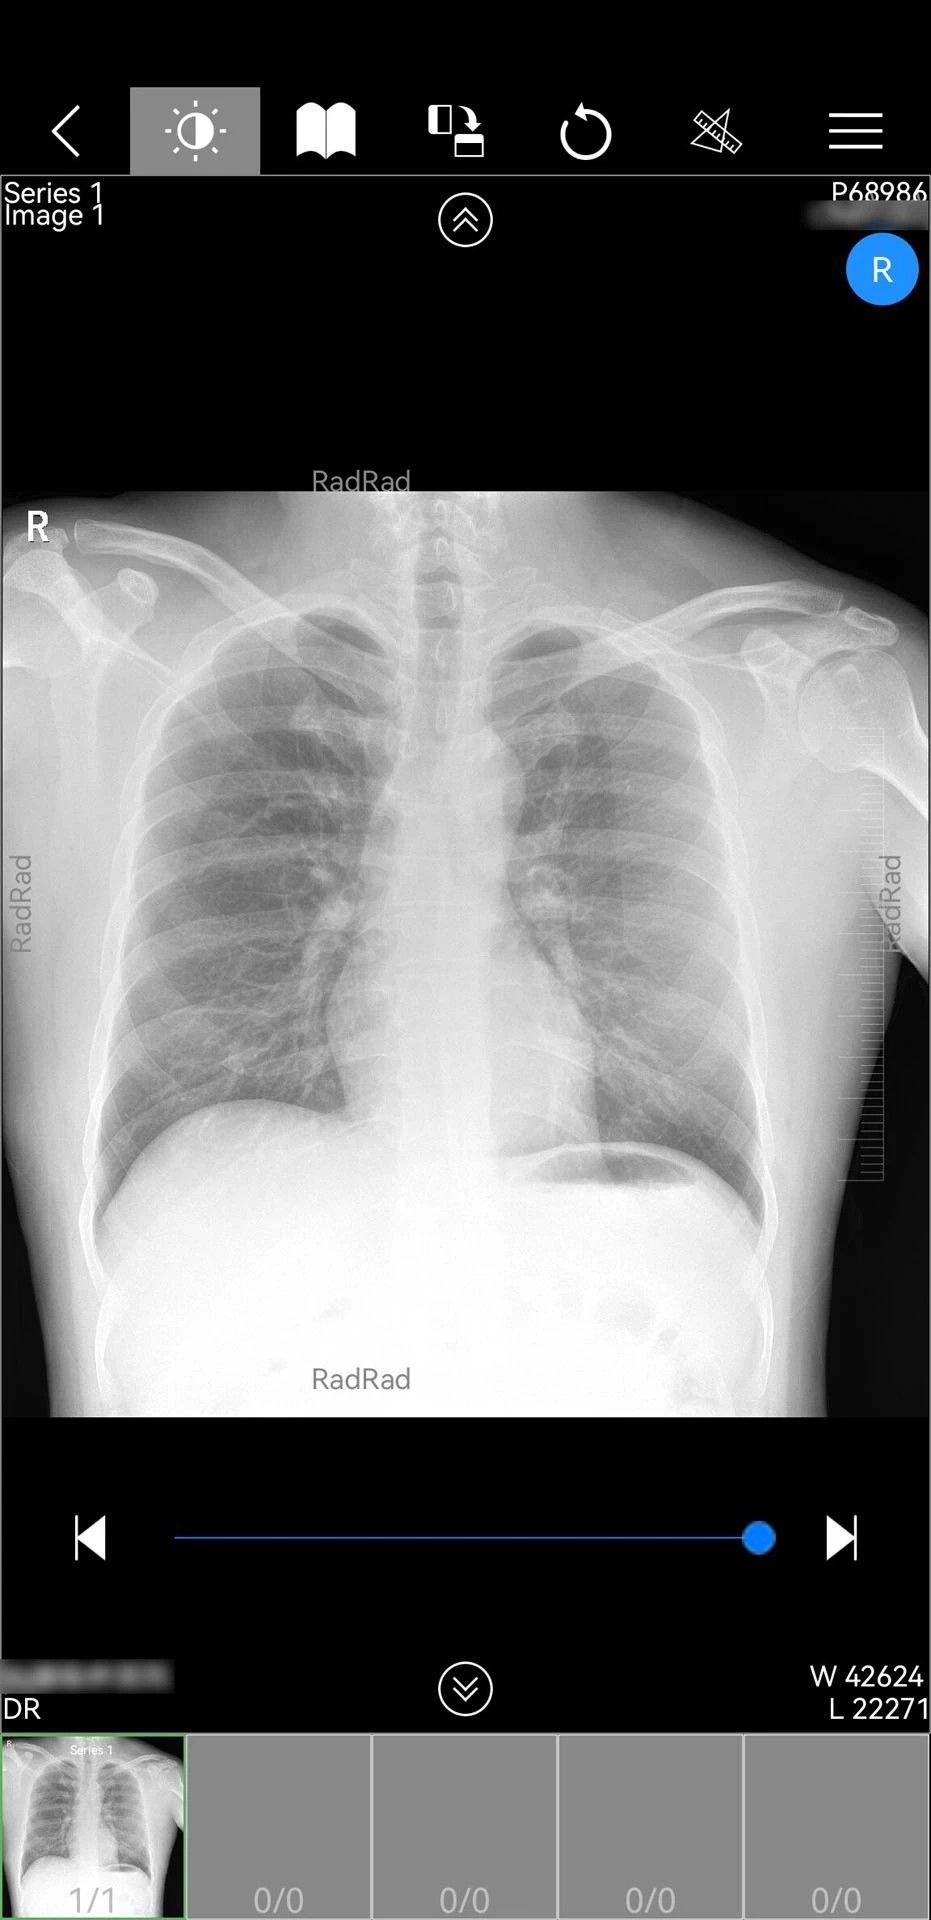

1. 影像调阅:支持快速调阅患者检查报告、电子胶片及PDF文档,医生可实时查看影像资料,无需依赖医院内网设备。

2. 影像调阅:登录后点击“患者管理”模块,选择需查看的患者,即可调阅其检查报告及影像资料,支持缩放、旋转等操作。